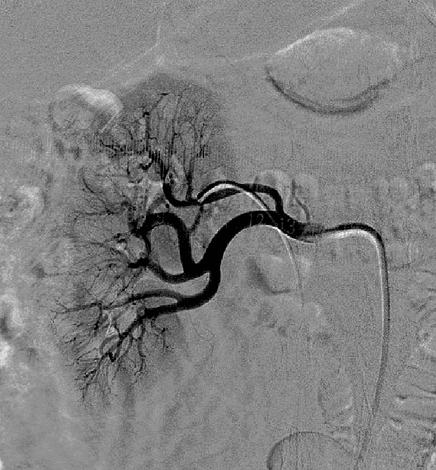

В 1989 году группа немецких исследователей во главе с Хартмутом Кирхгаймом опубликовала результаты эксперимента на животных, в котором симпатические нервы, идущие к почке, вывели из строя с помощью электрических импульсов. Эта «блокировка» привела к желаемому результату: производство ренина упало — и гипертония исчезла. При этом серьезных побочных эффектов лечения, таких, как раньше, не наблюдали. Исследователи сразу же подумали о возможности использовать этот метод для борьбы с гипертонией у людей. Понадобилось еще несколько десятилетий, чтобы довести технологию до ума и создать специальный катетер с миниатюрным передатчиком низкочастотных радиоволн, действующим по специальному алгоритму. Он вводится в почечную артерию пациента для того, чтобы воздействовать на нервные волокна, находящиеся рядом с сосудом с внешней стороны. Сегодня это уже не называют операцией — бескровную процедуру выполняет интервенционный кардиолог.